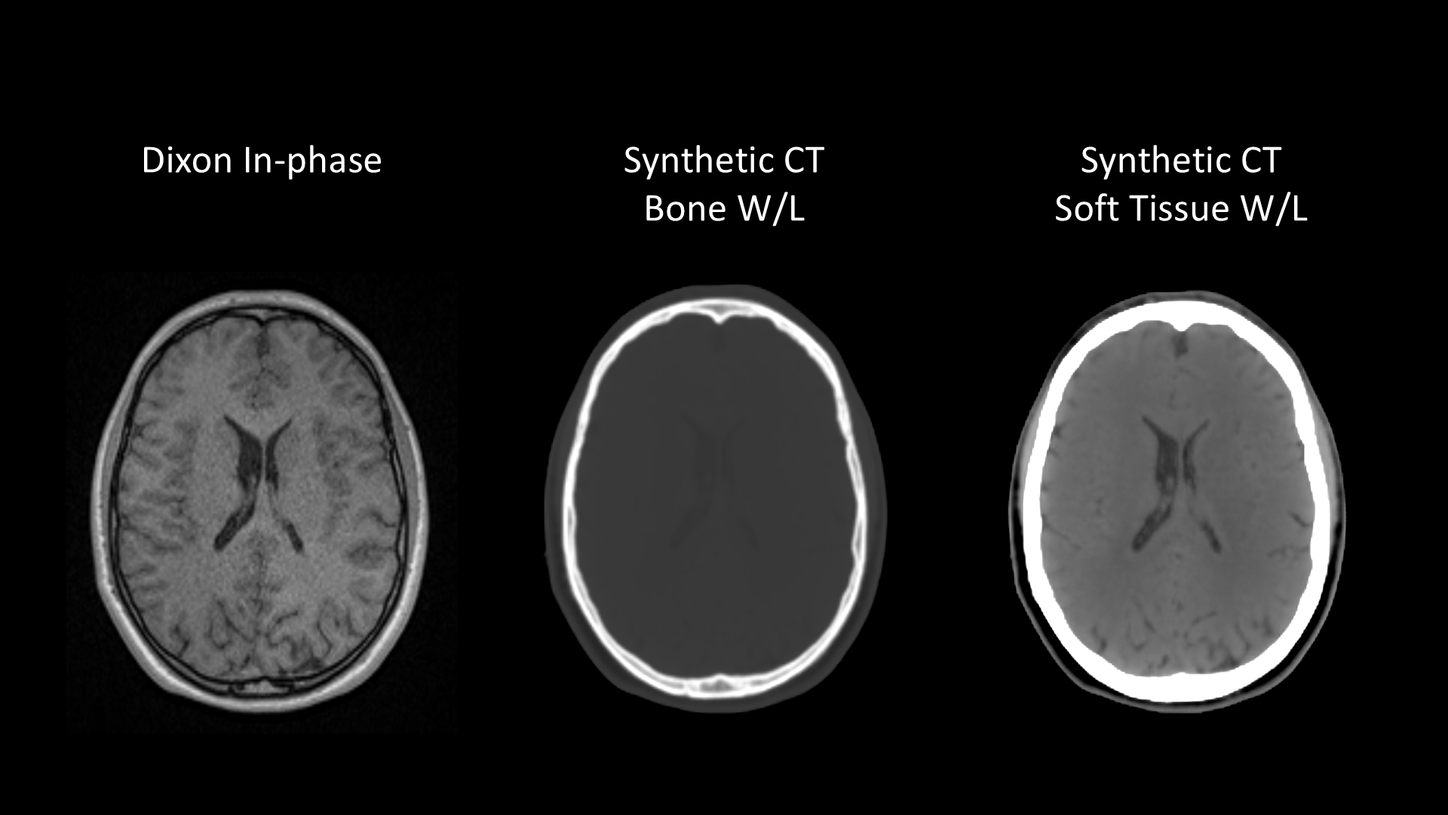

MR-based Synthetic CT offers the possibility of combining the superior soft-tissue contrast of MRI for organs-at-risk and target delineation with dosimetric planning. An MR-only workflow eliminates the need for CT to MRI registration, reducing systematic registration errors and unnecessary ionizing radiation from CT scans.

Discover our MR-only workflow for brain and pelvis.